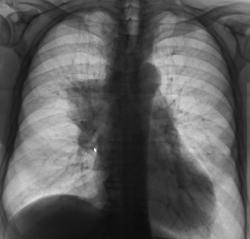

После взятия поциента "на контроль" произведи стандартное дообследование. Пациент жалоб не предъявляет, обращает внимание на небольшую одышку и "сухой" непродуктивный кашель. Произведено стандартное дообследование.

деформация правого корня. Он смещён немного вверх. Картина похоже на течение онкопроцесса.

Новообразование в области правого верхнедолевого бронха, центральная форма, ателектаз или обструктивный пневмонит в третьем сегменте, лимфангит во всей доле, расширение вехнего средостения вправо - метастазы?

Валентин Львович, а Вы не хотите сделать боковую томограмму через тень (корень) и томограмму на правый в/долевой бронх. Потому как ни одной из томограмм ни тень, ни бронхи справа не в срезе, а есть у меня такое впечатление, что имеет место периферический узел в S3, проекционно накладывающийся на тень корня, кроме того, при таком конгломерате в корне, должна быть более выражена гиповентиляция...